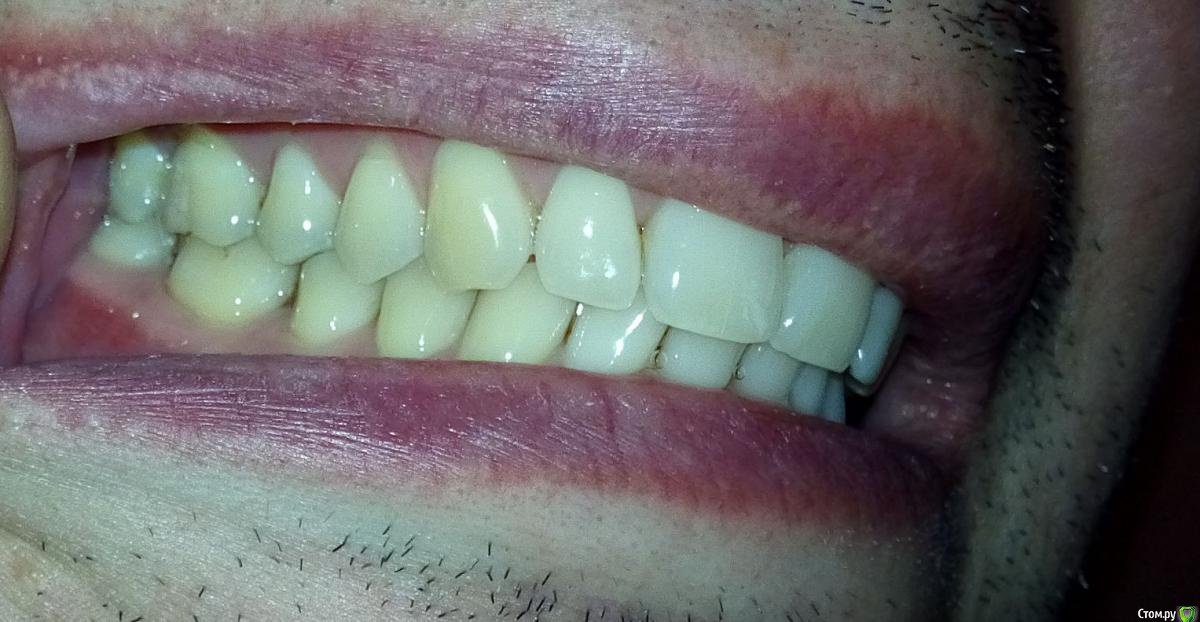

Мне 34 года. В связи с необходимостью перелечивания корней 36 и 37 зубов пришлось заменить металлокерамическую коронку. Однако, она мне не подошла: через несколько дней при смыкании нижняя челюсть начала какбы съезжать впред и влево, начали соприкасаться (ранее такого не было) передние левые зубы. Доктор объяснил это занижнием коронки в области 36 зуба. Сделали новую коронку, которую я носил неделю, но она мне тоже была неудобна (как бы завышала). Ее опять изменили, немного занизили. В результате почти месяц, ношения разных вариантов и в итоге:

* Ни с одним вариантом мне не было удобно. Сейчас не могу сомкнуть зубы, чтоб было удобно сразу и справа и слева как до лечения.

* раньше, со старыми коронками, жевать на эту сторону (где короник) было не совсем удобно. Сейчас, вроде бы, удобнее (субъективно).

-судя по бугристости на углах нижней челюсти и фасеткам стираемости  на многих зубах , Вы- бруксист! и еще тот!)  отсюда и симптоматика, и боли в мышцах.

Так же могу отметить, что форма старых 36 и 37 металлокерамичких коронок и старых зубов была плоскими (почти ровная площадка), стоматологи это свзязывали с тем, что зубы антагонисты соприкасались бугор-бугор, а не бугор-впадина. Самое инетерсное, что сейчас мне сделали бугры на коронке, которые попадают в впадины, но этот доцент, не зная какими были ранее зубы и коронки, констатировала, что ранее они были плоскими. Может стОит вернуться к старым формам? :wacko: